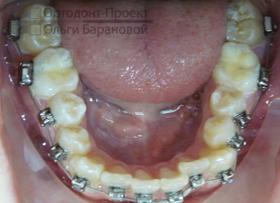

Брекеты Damon установлены:

![]() | ![]() |

На текущем этапе ортодонтического лечения использование брекетов сфокусировано на расширении зубного ряда в области второго и четвертого зубов, при этом на системе установлены специальные пружины.